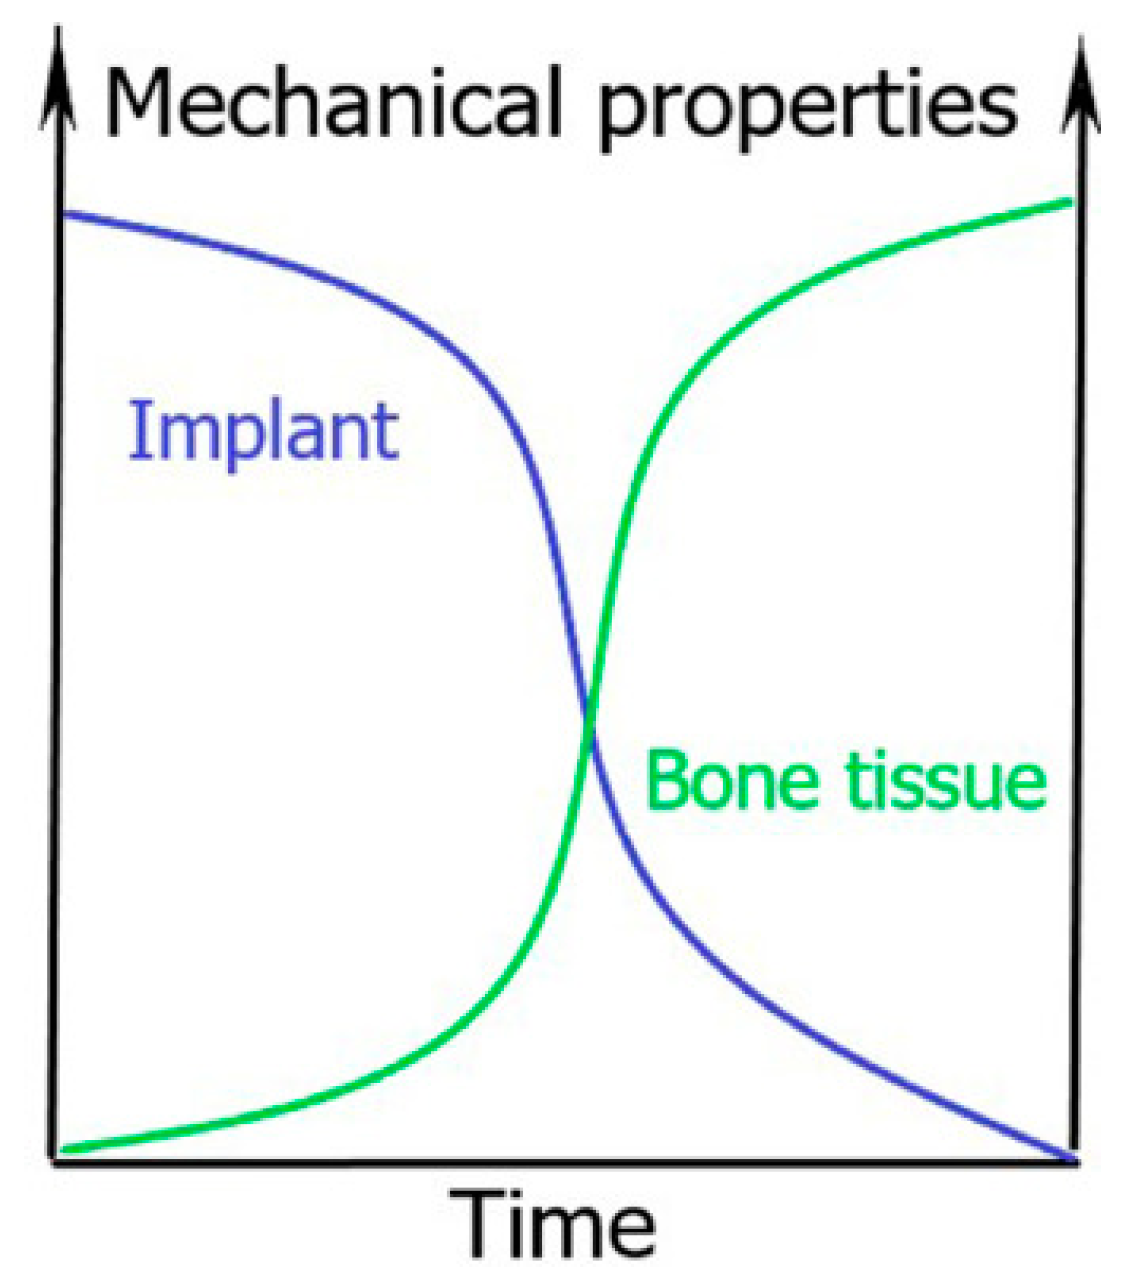

:1. General Introduction to Biodegradable Bone Implants